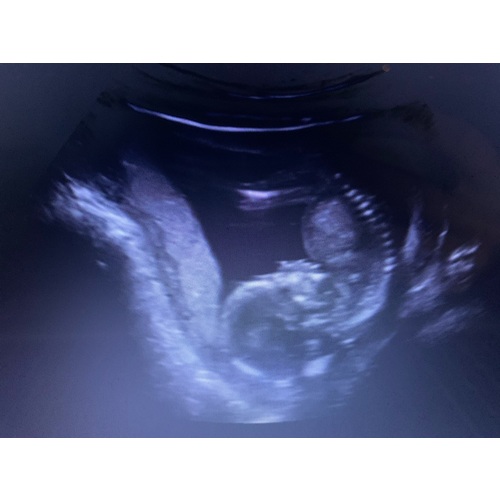

Ik voel ook zeer regelmatig precies wat jij beschrijft. Drink ook elke dag uit voorzorg een glas cranberry sap tegen blaasontsteking. Toevallig afgelopen donderdag een echo en moest ik weer ontzettend plassen maar ik was net 10 minuten eerder geweest en had niks meer gedronken.. Ik vertelde dat tegen de mevrouw van de echo, ga maar lekker liggen zei ze, dan zal ik eens kijken. Zo lag onze kleine erbij. Met het hoofdje op mijn blaas. Ook wilde die niet draaien en bleef het constant op de buik liggen😂.. Ze noemde het een buikslaper, lijkt op mij dus haha🙈

Heb ik ook. Gisteren tijdens de 20 wk echo bleek haar hoofdje heel diep achter mijn schaambot te liggen en op mijn blaas te drukken.